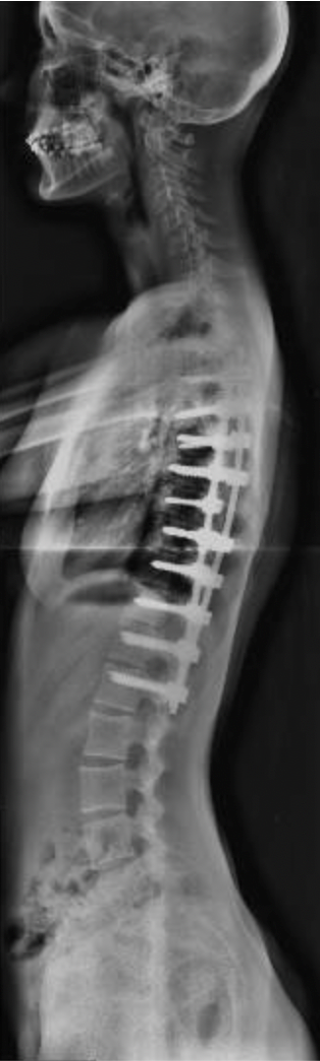

Morena

Inicio del tratamiento:

2018

Edad de la paciente:

10 años

Patología:

Escoliosis Idiopática del Adolescente.

Tratamiento: Uso de un corsé, y ejercicios indicados para prevenir la progresión de la curvatura. Al año: la escoliosis y el valor angular empeoraron significativamente En la primavera del 2020, plena pandemia, se llevó a cabo la corrección quirúrgica. Hoy, Morena ha logrado retomar sus actividades y actualmente juega al hockey. Su evolución refleja cómo, a pesar de las dificultades, se puede avanzar en el tratamiento de la escoliosis.